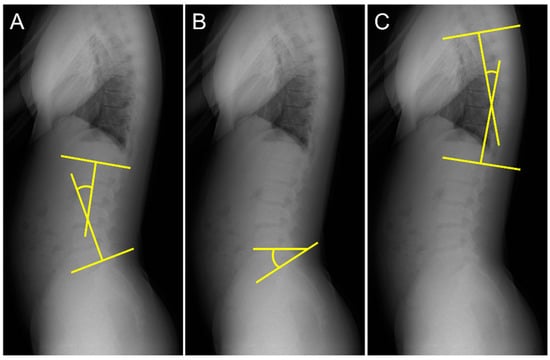

The lumbar lordosis angle (LL) was measured according to the method outlined in a previous study [18,19]. First, lines were drawn tangential to the superior endplate of L1 and inferior endplate of the L5. Second, perpendicular lines were drawn to each tangent. LL was defined as the acute angle formed by the intersection of the two perpendicular lines (Figure 2A). The sacral slope angle (SS) was measured using the procedure described in a previous study [20]. Lines were drawn tangentially to the superior endplate of S1 and horizontally. The SS was defined as the acute angle formed by these two lines (Figure 2B). The thoracic kyphosis angle (TK) was measured using the procedure described in a previous study [20]. First, lines were drawn tangential to the superior endplate of T5 and inferior endplate of T12. Second, lines perpendicular to each tangent were drawn. TK was defined as the acute angle formed by the intersection of the two perpendicular lines (Figure 2C).

Figure 2.

Measurement of spinal alignment. (A) Measurement of the lumbar lordosis angle (LL), (B) sacral slope angle (SS), and (C) thoracic kyphosis angle (TK).